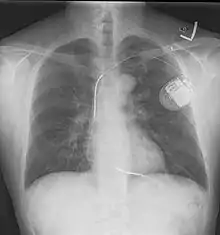

The process of implantation of an ICD system is similar to implantation of a pacemaker. In fact, ICDs are composed of an ICD generator and of wires. The first component or generator contains a computer chip or circuitry with RAM (memory), programmable software, a capacitor and a battery; this is implanted typically under the skin in the left upper chest. The second part of the system is an electrode wire or wires that, similar to pacemakers, are connected to the generator and passed through a vein to the right chambers of the heart. The lead usually lodges in the apex or septum of the right ventricle. Just like pacemakers, ICDs can have a single wire or lead in the heart (in the right ventricle, single chamber ICD), two leads (in the right atrium and right ventricle, dual chamber ICD) or three leads (biventricular ICD, one in the right atrium, one in the right ventricle and one on the outer wall of the left ventricle). The difference between pacemakers and ICDs is that pacemakers are also available as temporary units and are generally designed to correct slow heart rates, i.e. bradycardia, while ICDs are often permanent safeguards against sudden life-threatening arrhythmias.

Initially ICDs were implanted via thoracotomy with defibrillator patches applied to the epicardium or pericardium. The device was attached via subcutaneous and transvenous leads to the device contained in a subcutaneous abdominal wall pocket. The device itself acts as an electrode. Most ICDs nowadays are implanted transvenously with the devices placed in the left pectoral region similar to pacemakers. Intravascular spring or coil electrodes are used to defibrillate. The devices have become smaller and less invasive as the technology advances. Current ICDs weigh only 70 grams and are about 12.9 mm thick.